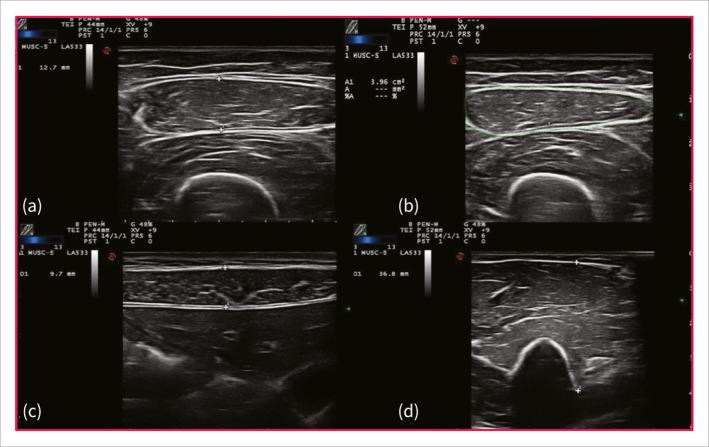

METHODS

153 consecutive patients were included, 100 in the training cohort and 53 in the study cohort. Three superficial muscles (rectus femoris = RF, rectus abdominis = RA, and biceps brachii = BB) were selected for the detection of sarcopenia using muscle ultrasound (US). The training cohort consisted of consecutive patients with or without IBD and was used to evaluate the feasibility and inter- and intra-observer variability of the US measurement. The study cohort consisted of only IBD patients and served to test US diagnostic accuracy. In the latter, muscle US, bioelectrical impedance analysis (BIA), and magnetic resonance imaging (MRI) were used to measure muscle parameters.

RESULTS

Sarcopenia prevalence in IBD patients was 50%. Muscle US showed excellent inter-rater and intra-rater reliability (ICC >0.95) and a good diagnostic accuracy in detecting sarcopenia compared to BIA with area under the receiver operating characteristic curve (AUROC) values of 80% and 85% for RA and BB thickness, respectively. Moreover, an Ultrasound Muscle Index (USMI) was defined as the sum of the RA, BB, and RF thickness divided by the square of the patient's height, resulting in an AUROC of 81%. Muscle thresholds for sarcopenia were detected, with RA and USMI values correlated with the highest positive (84.3%) and negative (99%) predictive values, respectively. Additionally, the agreement between the US and MRI measurements of RA was excellent (ICC 0.96).

方法

共纳入 153 例连续患者,其中 100 例纳入训练队列,53 例纳入研究队列。使用肌肉超声(US)检测 3 块表浅肌肉(股直肌=RF、腹直肌=RA 和肱二头肌=BB)是否存在肌肉减少症。训练队列由连续的 IBD 患者和非 IBD 患者组成,用于评估 US 测量的可行性和观察者内及观察者间的变异性。研究队列仅由 IBD 患者组成,用于测试 US 的诊断准确性。在后者中,使用肌肉 US、生物电阻抗分析(BIA)和磁共振成像(MRI)测量肌肉参数。

结果

IBD 患者肌肉减少症的患病率为 50%。肌肉 US 显示出极好的观察者间和观察者内可靠性(ICC>0.95),与 BIA 相比,RA 和 BB 厚度的曲线下面积(AUROC)值分别为 80%和 85%,具有良好的诊断准确性。此外,定义超声肌肉指数(USMI)为 RA、BB 和 RF 厚度之和除以患者身高的平方,得到的 AUROC 为 81%。检测到肌肉减少症的肌肉阈值,RA 和 USMI 值与最高的阳性(84.3%)和阴性(99%)预测值相关。此外,US 和 MRI 测量 RA 的一致性非常好(ICC 0.96)。